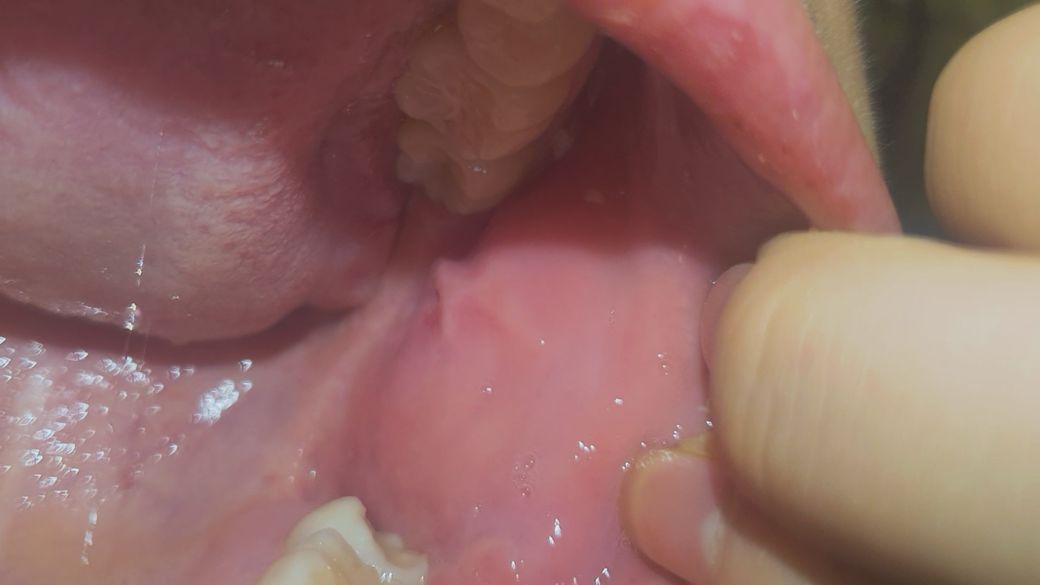

입안쪽에 염증인지 헐은건지 모르겠는데 뭐가 도톰해요

어제부터 갑자기 입안쪽에 뭐가 났어요 뭐가 튀어나왔도 따가워요..병원가야하나요?아니면 약국에서 그냥약만 사도 되나요?무슨 약 사야하죠?? 따가워서 밥을 잘못먹겠어요..

사진으로 명확히 모르겠지만,, 입안의 대부분의 병변은 며칠지나면 좋아집니다. 병변이 심해보이지도 않네요.

특별히 해줄수 있는 방법이 없고,, 약국에서 입안에 바르는연고 사용해볼수는 있겠습니다.

저절로 좋아지니까 너무 걱정안해도 되겠습니다.